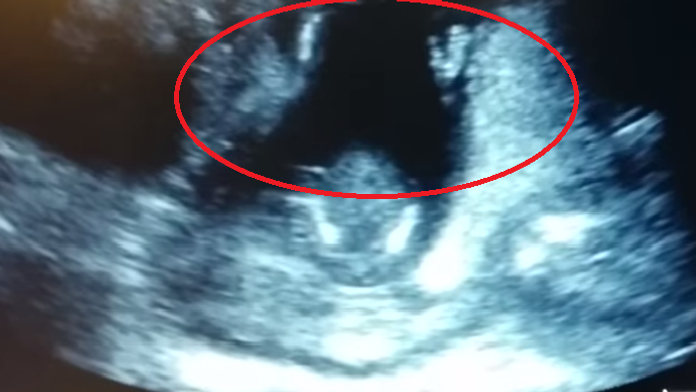

Prekvapenie na ultrazvuku: Len 14-týždňový plod začal tlieskať

Čarovný moment zachytilo ultrazvukové vyšetrenie. Na monitore sa zdalo, že len 14-týždňový plod si začal tlieskať po tom, ako jeho zaspievala známu pesničku „keď si šťastný tlieskaj rukami".

Rodičia z Veľkej Británie na tento ultrazvuk asi nikdy nezabudnú. Hneď ako ich dieťa začalo tlieskať, sa do spevu zapojili otec aj lekár. Video sa šíri na internete. V pozadí je počuť šťastný smiech rodičov.